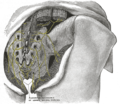

صورة لحوض ذكر (العجز في الوسط) | |